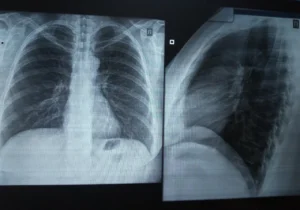

Рентген легких: что нужно знать о процедуре для здоровья ваших легких

Рентген легких – это один из наиболее распространенных и доступных методов диагностики, позволяющий оценить состояние легких и выявить различные заболевания органов грудной клетки. Этот метод основан на использовании рентгеновских лучей, которые проникают через ткани тела и создают изображение на специальной пленке или цифровом детекторе. Рентген легких позволяет врачам увидеть изменения в легких, сердце, кровеносных сосудах …